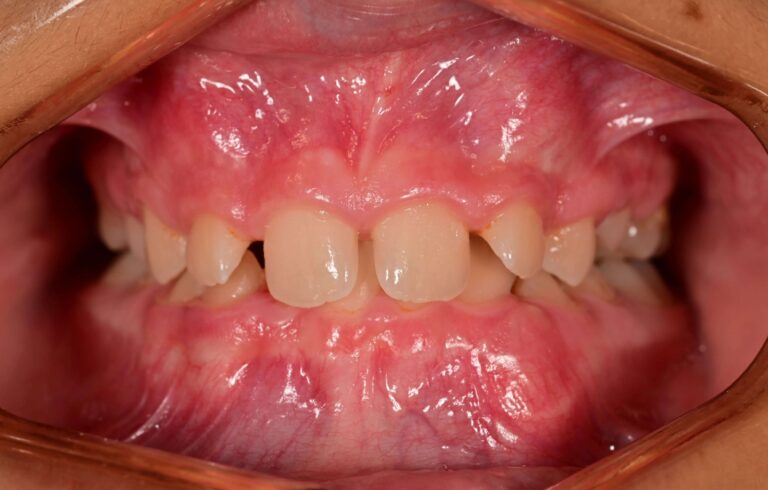

Кръстосана захапка (Crossbite)

Кръстосаната захапка е ортодонтски проблем, при който горните зъби застават зад долните. Дължи се на несъответствие в челюстите, което поражда неправилно подреждане на зъбите (включително млечните зъби). Може да засегне един, няколко зъба или цялото съзъбие. Има два основни вида кръстосана захапка:

Задна кръстосана захапка – По-често срещана от двата вида. Възниква, когато горните задни зъби попадат зад долните задни зъби.

Предна кръстосана захапка – среща се по-рядко. При затворена уста горните предни зъби са разположени зад долните предни зъби.

Усложнения, които могат да настъпят – ако не се лекуват, кръстосаните захапки могат да доведат до изместване на челюстта на едната страна, което от своя страна води до неравномерен растеж на челюстта и износване на зъбния емайл. Кръстосаната захапка често води до заболявания на венците.